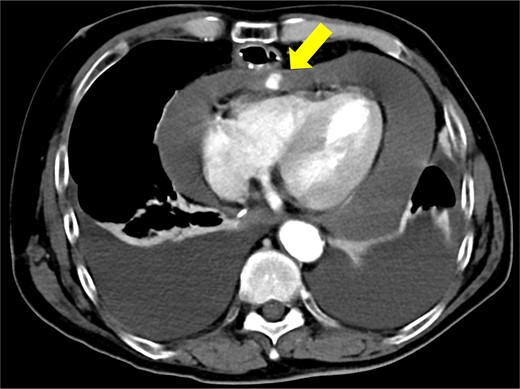

Biopsy confirmed the diagnosis of squamous cell carcinoma. Contrast-enhanced computed tomography (CT) showed wall thickening in the lower thoracic esophagus. No enlarged lymph nodes and distant metastases were found. There was no evidence of pericardial effusion, or significant coronary aneurysm (Fig. 1). No abnormal findings were observed on 12-lead electrocardiography or echocardiography. Spirometry revealed obstructive ventilatory impairment, and thus, long-acting beta-agonist and muscarinic antagonist inhalation were initiated.

Preoperative contrast-enhanced computed tomography shows no evidence of pericardial effusion, or significant coronary aneurysm.